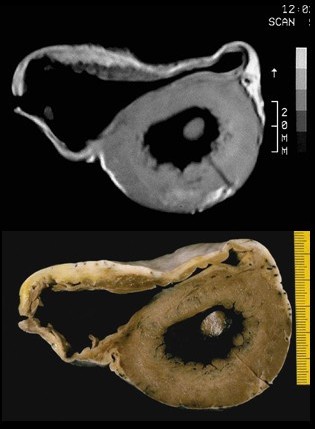

Kardiale Magnetresonanztomographie

Eine kardiale MRT sollte bei Patienten in der initialen Beurteilung erwogen werden. Die Kardio-MRT ist der 2D-Echokardiographie im Nachweis einer apikalen und anterolateralen Hypertrophie sowie von Aneurysmata und Thromben überlegen.

Bildgebung

© wikipedia.org/ Thiene G, Corrado D, Basso C. Arrhythmogenic right ventricular cardiomyopathy/dysplasia. Orphanet J Rare Dis. 2, 45. 2008. doi:10.1186/1750-1172-2-45. PMID 18001465., CC BY 2.0